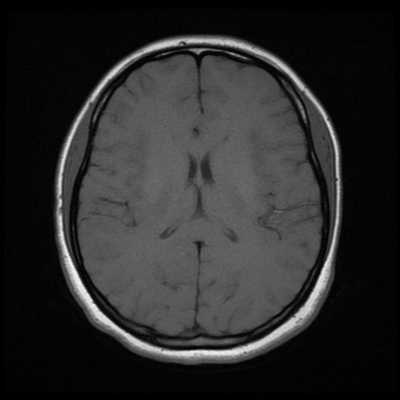

Как выглядит снимок МРТ головного мозга

Классический пример МРТ снимков головного мозга показан на рисунках ниже. Магнитно-резонансная томография выполняется в поперечной (или аксиальной - рисунок снизу) и продольной (или сагиттальной — рисунок сверху) плоскостях.

Исследование выполняется в нескольких режимах. Основные из них Т1 и Т2. Изображения, полученные в данных режимах, часто также называют Т1-взвешенными или Т2-взвешенными снимками. Изображения, показанные выше, сделаны в Т1-режиме.

Главное отличие этих режимов - в том, как на снимках отображается жидкость и воздух. В Т1 режиме ткани, содержащие большое количество воды, имеют более темную окраску, в то время как в Т2 режиме они яркие, светлые. Это легко понять, посмотрев на снимки выше - глазные яблоки визуализируются в виде светлых парных округлых образований с одной стороны яркие и светлые, с другой - темные. Следовательно, снимок справа сделан в Т1 режиме, снимок слева - в Т2. Также существует разница в том, как в этих режимах отображается серое вещество головного мозга. В Т2 режиме оно светлее, чем белое вещество.